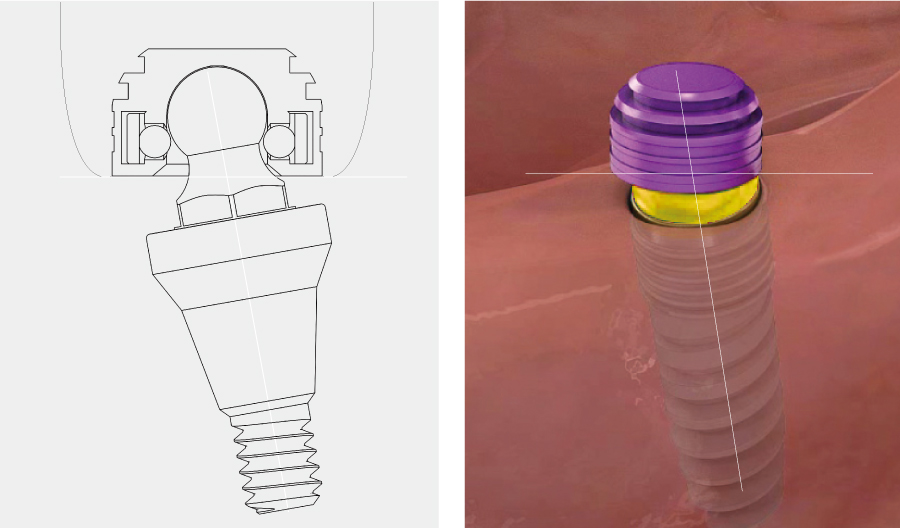

부분 상세설명 소모품교체 없음

소모품교체 없음Titanium housing과 Zirconia ball, Nitinol pan spring으로 이루어져 있어 소모품 교체 없이 장기간 사용이 가능하다.

Fixture 보호Locking 시 지대주와 housing 사이에 0.8mm 가량의 공간이 부여되어 의치 기능 시 연조직의 위축량을 보상함으로써 지대주에 가해지는 힘을 줄일 수 있다.

편측 20도 각도 보상

편측 20도 각도 보상지대주의 groove와 housing ball & spring이 체결되는 ‘EZ LOCKING 방식’에 의해 fixture의 식립각도를 20도까지 보상할 수 있다. (각도별 housing positioner 이용)